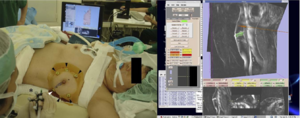

Treatment Planning and Delivery of Whole Brain Irradiation with Hippocampal Avoidance in Rats

Publication: PLoS One. 2015 Dec 4;10(12):e0143208. PMID: 26636762 | PDF Authors: Cramer CK, Yoon SW, Reinsvold M, Joo KM, Norris H, Hood RC, Adamson JD, Klein RC, Kirsch DG, Oldham M. Institution: Department of Radiation Oncology, Duke University Medical Center, Durham, NC, USA. Background/Purpose: Despite the clinical benefit of whole brain radiotherapy (WBRT), patients and physicians are concerned by the long-term impact on cognitive functioning. Many studies investigating the molecular and cellular impact of WBRT have used rodent models. However, there has not been a rodent protocol comparable to the recently reported Radiation Therapy Oncology Group (RTOG) protocol for WBRT with hippocampal avoidance (HA) which is intended to spare cognitive function. The aim of this study was to develop a hippocampal-sparing WBRT protocol in Wistar rats. Methods: The technical and clinical challenges encountered in hippocampal sparing during rat WBRT are substantial. Three key challenges were identified: hippocampal localization, treatment planning, and treatment localization. Hippocampal localization was achieved with sophisticated imaging techniques requiring deformable registration of a rat MRI atlas with a high resolution MRI followed by fusion via rigid registration to a CBCT. Treatment planning employed a Monte Carlo dose calculation in SmART-Plan and creation of 0.5 cm thick lead blocks custom-shaped to match DRR projections. Treatment localization necessitated the on-board image-guidance capability of the XRAD C225Cx micro-CT/micro-irradiator (Precision X-Ray). Treatment was accomplished with opposed lateral fields with 225 KVp X-rays at a current of 13mA filtered through 0.3 mm of copper using a 40x40 mm square collimator and the lead blocks. A single fraction of 4Gy was delivered (2Gy per lateral field) with a 41 second beam on time per field at a dose rate of 304.5 cGy/min. Dosimetric verification of hippocampal sparing was performed using radiochromic film. In vivo verification of HA was performed after delivery of a single 4Gy fraction either with or without HA using γ-H2Ax staining of tissue sections from the brain to quantify the amount of DNA damage in rats treated with HA, WBRT, or sham-irradiated (negative controls). Results: The mean dose delivered to radiochromic film beneath the hippocampal block was 0.52Gy compared to 3.93Gy without the block, indicating an 87% reduction in the dose delivered to the hippocampus. This difference was consistent with doses predicted by Monte Carlo dose calculation. The Dose Volume Histogram (DVH) generated via Monte Carlo simulation showed an underdose of the target volume (brain minus hippocampus) with 50% of the target volume receiving 100% of the prescription isodose as a result of the lateral blocking techniques sparing some midline thalamic and subcortical tissue. Staining of brain sections with anti-phospho-Histone H2A.X (reflecting double-strand DNA breaks) demonstrated that this treatment protocol limited radiation dose to the hippocampus in vivo. The mean signal intensity from γ-H2Ax staining in the cortex was not significantly different from the signal intensity in the cortex of rats treated with WBRT (5.40 v. 5.75, P = 0.32). In contrast, the signal intensity in the hippocampus of rats treated with HA was significantly lower than rats treated with WBRT (4.55 v. 6.93, P = 0.012). Conclusion: Despite the challenges of planning conformal treatments for small volumes in rodents, our dosimetric and in vivo data show that WBRT with HA is feasible in rats. This study provides a useful platform for further application and refinement of the technique. Funding:

|

MRI with labeled structures from atlas registered to the CBCT. Registration was carried out with the open source imaging tool 3D Slicer, Version 4.4.0. |